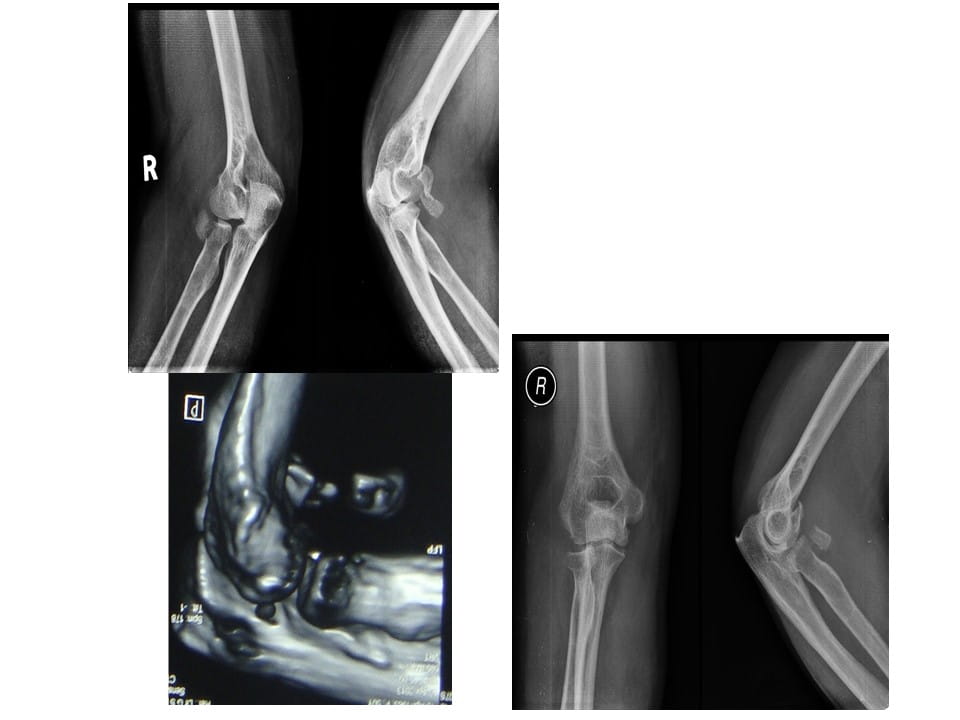

Terrible Triad